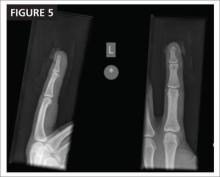

X-rays (FIGURE 5) reveal a distal tuft fracture. The patient’s main concern is the pain, and he asks what you can do to relieve it.

This patient has a closed fracture of the distal phalanx, called a tuft fracture, and a sub-ungual hematoma, evident from the x-ray and the physical presentation.